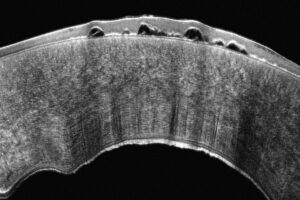

Hoge-resolutie OCT-technologie maakt gedetailleerde visualisatie van de corneale structuren mogelijk, inclusief nauwkeurige meting van de epitheliale dikte. Deze meting is cruciaal voor de vroege detectie van corneale ectasie. Epitheliale diktemapping ondersteunt bovendien de chirurgische planning, wat bijdraagt aan optimale resultaten van refractiechirurgie. OCT-beeldvorming is bovendien essentieel voor:

- postoperatieve zorg;

- het volgen van genezing;

- en het opsporen van complicaties na LASIK of keratoplastiek.

- Epitheliale diktemapping